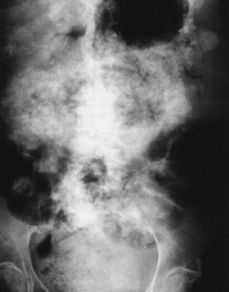

La radiografía simple de abdomen muestra múltiples áreas calcificadas distribuidas difusamente (Fig. 1). Se realiza TC abdominal donde se define una masa pélvica, heterogénea, parcialmente calcificada, con bordes mal definidos, sugestiva de neoplasia ginecológica. También se observa engrosamiento mesentérico y de épiplon mayor, parcialmente calcificado (Fig. 2), calcificaciones perihepáticas, periesplénicas y ascitis, (Fig. 3). Hallazgos sugestivos de carcinomatosis peritoneal abundantemente calcificada.

Figura 2.Pastel omental con amplias zonas de calcificación. Ascitis. Adenopatía interaortocava con calcio en su interior.